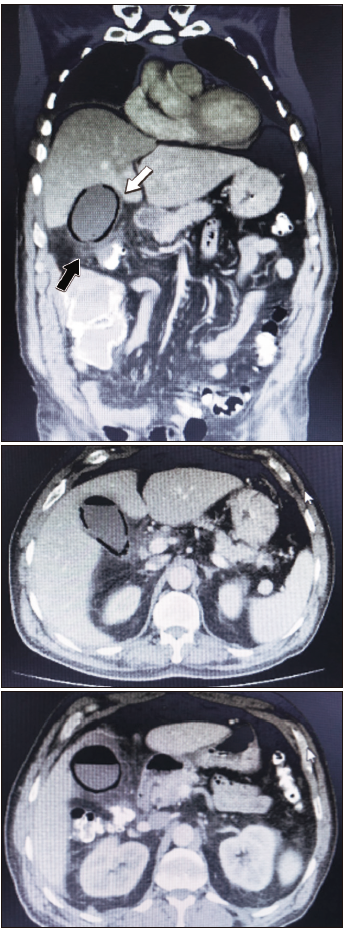

Hombre de 55 años, sin antecedentes de clínicos de relevancia, que ingresó con dolor abdominal con tres días de evolución localizado en hipocondrio derecho. Al momento del ingreso el paciente se presentaba estable, con dolor en la palpación en la parte superior del abdomen y sin irritación peritoneal. En el hemograma se detectó leucocitosis con neutrofilia; los análisis no mostraron otras alteraciones. Presentó una radiografía simple de abdomen dentro de parámetros normales. Se realizó una ecografía abdominal que mostró vesícula distendida, de paredes regulares y de 3,8mm; en bacinete presentó cálculo de 13mm, barro biliar y microlitiasis. Dentro de la vesícula se observó una banda de gas compatible con CE; vía biliar no dilatada. (Figura 1) Se complementó con una TC de abdomen y se confirmó el diagnóstico de CE sin neumoperitoneo. (Figura 2)

Figura 1. Ecografía abdominal. Banda hiperecogénica (flecha blanca) atribuible a gas

en el interior de la vesícula biliar

Figura 2. TC de abdomen con contraste endovenoso. Presencia de burbujas aéreas en la

pared vesicular (flecha blanca) asociada a densificación de los planos grasos adyacentes (flecha

negra)